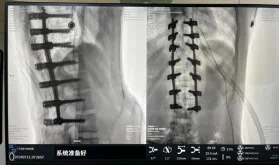

圖為置釘后

此次在充分保證患者安全和手術效果的前提下使用機器人輔助下手術的成功實施,大大降低了高難度手術的風險,并進一步減輕了患者手術創傷、縮短了康復時間。這也標志著南方醫院贛州醫院脊柱外科治療個性化、精準化、智能化水平進一步提升。